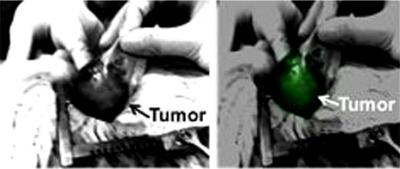

With a new technique, researchers at the University of Pennsylvania have established a new strategy to help surgeons see the entire tumor in the patient, increasing the likelihood of a positive outcome. This approach relies on an injectable dye that accumulates in cancerous tissues much more so than normal tissues. When the surgeon shines an infrared light on the cancer, it glows, allowing the surgeon to remove the entire malignancy.

Seeking an alternative, Holt, Singhal and colleagues turned to near-infrared, or NIR, imaging. They chose to test the only Food and Drug Administration-approved contrast agent for NIR, a dye called indocyanine green, or ICG, that fluoresces a bright green under NIR light. ICG concentrates in tumor tissue more than normal tissue because the blood vessels of tumors have so-called "leaky" walls from growing quickly.

Next the researchers evaluated the technique in eight client-owned dogs, of various breeds and sizes, that had naturally occurring lung cancer and were brought to Penn Vet for surgery. They received ICG intravenously a day before surgery, then surgeons used NIR during the procedure to try to visualize the tumor and distinguish it from normal tissue.

"It worked," Holt said, the tumors fluorescing clearly enough to permit the surgeon to rapidly distinguish the cancer during surgery. "And because it worked in a spontaneous large animal model, we were able to get approval to start trying it in people."

All of the tumors strongly fluoresced under the NIR light, confirming that the technique worked in human cancers.